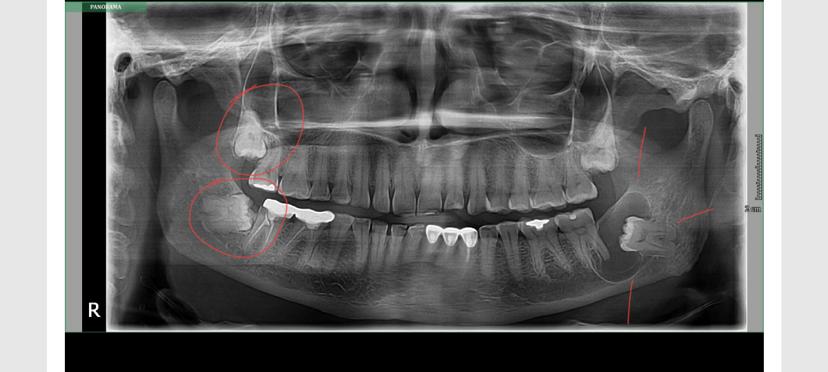

Bone Loss